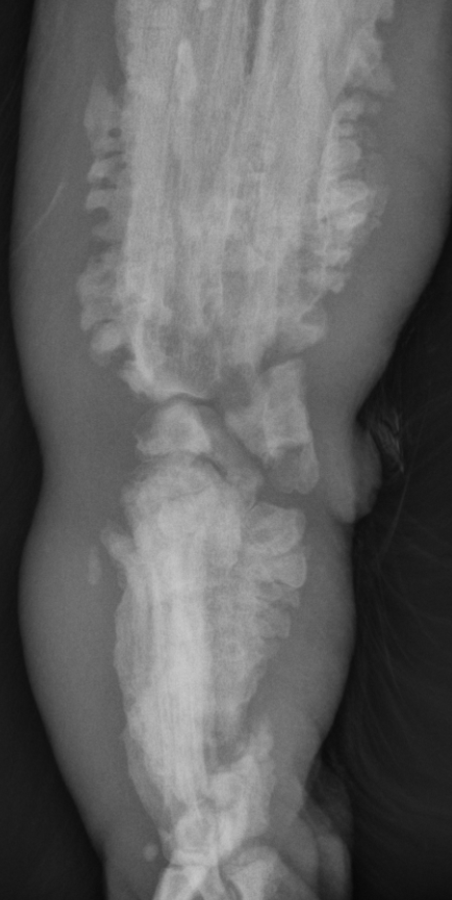

What is shown in these radiographs?

retained cartilaginous core

angular deformity of radius and ulna due to retained cartilaginous core